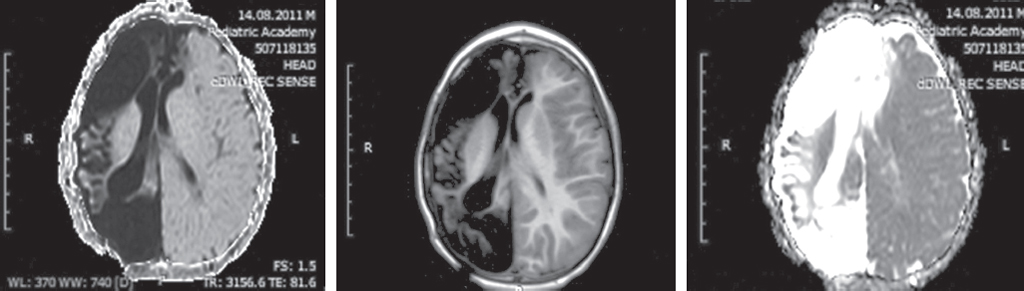

Анамнез болезни: в возрасте 4 мес. на фоне гастроэнтерита у ребенка развился геморрагический синдром. Госпитализирован по месту жительства (Владивосток), проведена компьютерная томография головного мозга и выявлена правополушарная субдуральная гематома. Проведено нейрохирургическое вмешательство. Отмечались ранние судороги в послеоперационном периоде. Через 3 нед. появились гематомы на коже живота, бедер, рук. Проведено гематологическое обследование, предположительный диагноз — гемофилия. На контрольной КТ головного мозга выявлены три свежие гематомы. Ребенок повторно оперирован, затем направлен в онкологический центр (Москва), исключена патология сосудисто-тромбоцитарного и коагуляционного звеньев гемостаза. Установлен окончательный диагноз поздней геморрагической болезни новорожденных. В дальнейшем проводилась реабилитационная терапия по поводу коррекции левостороннего гемипареза. Дебют приступов в 2017 г. (в возрасте 6 лет). Назначен леветирацетам, на этом фоне отмечалась положительная динамика, приступы купированы. Рецидив приступов в мае 2018 г. (на фоне приема леветирацетама в дозе 900 мг в сутки), постепенно количество приступов нарастало, до двух эпизодов в сутки. К терапии добавлен вальпроат в дозе 30 мг/кг, эффекта не отмечено. На ЭЭГ регистрировались разряды эпилептиформной активности над левым полушарием с диффузным распространением. МРТ головного мозга проведена в августе 2019 г.: МР-картина обширной зоны лейкоэнцефаломаляции, субтотально занимающей правую гемисферу и парасаггитальные отделы левой лобной доли. Невыраженные атрофические изменения правого гиппокампа правого миндалевидного тела (рис. 1, 2). Введен окскарбазепин (Трилептал, 20 мг/кг), отменена вальпроевая кислота (Депакин). На фоне отмены вальпроевой кислоты — улучшение общего состояния, ребенок стал более активным, внимательным, однако частота приступов осталась прежней. К схеме лечения добавлен ламотриджин, пациент стал возбудим, препарат отменен. Введен руфинамид (Иновелон в дозе 800 мг в сутки), на этом фоне в течение 5 мес. приступов не было. С октября 2020 г. пароксизмы возобновились.

Рис. 1. Магнитно-резонансная томограмма пациента. Коронарные срезы, Т2 взвешенное изображение. Лейкоэнцефаломаляция правой гемисферы и парасаггитальных отделов левой лобной доли

Fig. 1. MRI of a patient М. Coronary sections, T2 VI. Leukoencephalomalacia of the right hemisphere and parasagittal parts of the left frontal lobe

Рис. 2. Магнитно-резонансная томограмма пациента. 4 мес. Аксиальные срезы. Кистозно-атрофические изменения в правой гемисфере

Fig. 2. MRI of a patient. Axial sections, T1 VI, T2 VI, Flair. the cystic-atrophic changes in the right hemisphere

ЭЭГ от 27.04.2021. Проведена запись в состоянии спокойного бодрствования при открытых глазах. Отмечается выраженная асимметрия вольтажа, с угнетением физиологической активности над левым полушарием. Над левым полушарием достаточно устойчивый альфа-ритм 8 Гц. Эпилептиформная активность в виде нечастых одиночных и сдвоенных разрядов, по морфологии — доброкачественных эпилептических разрядов детского возраста над левым полушарием, с инверсией фазы над задневисочными отведениями и распространением по полушарию и редко — контрлатерально. Заключение: асимметрия вольтажа. Эпилептиформная активность в виде нечастых одиночных, сдвоенных, реже кластерных разрядов над левым полушарием, инверсия над задневисочными отведениями. Диагноз: «Фокальная структурная эпилепсия, фармакорезистентная. STARTL-приступы. Левосторонний гемипарез. Задержка психомоторного развития» (рис. 1, 2).